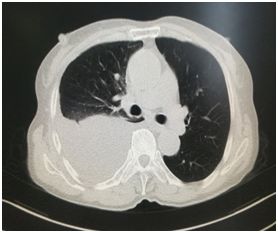

患者某老年男性,因胸闷喘憋入院,胸部CT提示右侧大量液胸(图1),在外院抽液后胸腔积液反复出现,长期诊断不清,家属非常着急,入科后与患者及家属沟通后果断选择了局麻胸腔镜检查,发现肺表面散在粟粒样结节,遂行脏层胸膜结节活检,术后3天病理即提示腺癌,在我院应用肺癌靶向药物克唑替尼治疗。目前健康生活已两年余,近日复查胸部CT肺部肿瘤消失,未见胸腔积液(图2)

图1